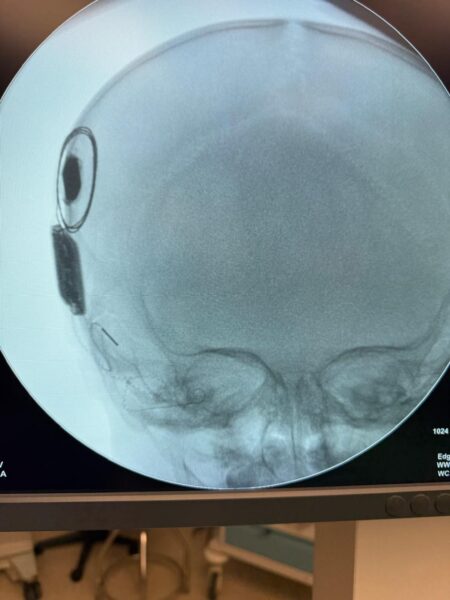

रामकृष्ण CARE हॉस्पिटल, रायपुर में पहली बार दुनिया का पहला और एकमात्र स्मार्ट, नेक्स्ट-जनरेशन Nexa Cochlear Implant 12/04/2026 को 15 महीने की एक नन्ही बच्ची पर सफलतापूर्वक किया गया।

कोक्लियर इम्प्लांट दो भागों से मिलकर बना होता है—एक आंतरिक इम्प्लांट, जिसे सर्जरी के माध्यम से कान के अंदर लगाया जाता है, और एक बाहरी साउंड प्रोसेसर, जिसे घाव ठीक होने के बाद पहना जाता है। यह बाहरी प्रोसेसर मैग्नेट के माध्यम से अंदरूनी इम्प्लांट से जुड़ा होता है।

सर्जरी के दौरान, Nexa इम्प्लांट को स्मार्ट नेविगेशन सिस्टम की मदद से कोक्लिया में स्थापित किया जाता है, जो रियल-टाइम इंट्रा-ऑपरेटिव फीडबैक प्रदान करता है। इससे इलेक्ट्रोड की सटीक प्लेसमेंट और डिवाइस की बेहतर कार्यक्षमता सुनिश्चित होती है।